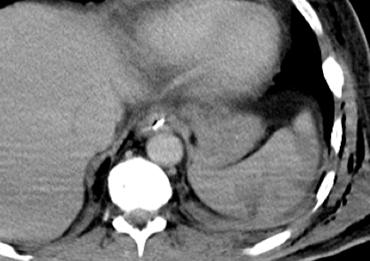

Trước tiên hãy quan sát các hình ảnh bên trái của bệnh nhân bị chấn thương gan.

Các dấu hiệu CT trong trường hợp này là gì?

Các dấu hiệu bao gồm:

- Mất tưới máu hoàn toàn thùy gan phải.

- Vùng ngấm thuốc cản quang (contrast blush) trong nhu mô gan, đồng thời lan ra ngoài bờ bên của gan.

- Tràn máu ổ bụng (Hemoperitoneum).

- Một vùng ngấm thuốc cản quang thứ hai ở mức thấp hơn.